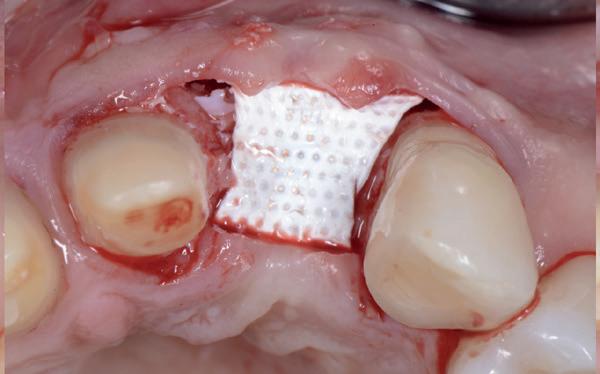

Het botdefect wordt geaugmenteerd met een allograft (Biohorizons MinerOss A). Om dit volume te stabiliseren, wordt een titanium versterkt membraan aangebracht (Cytoplast ti-reinforced d-PTFE membraan) met daaroverheen een collageen membraan (Mem-Lok collagen matrix). Na sluiting van de flap wordt de 4-delige PMMA brug, die al is gefreesd in het laboratorium naar aanleiding van de planning, gerelined en geplaatst met een tijdelijk cement (foto 9-14).

Er wordt besloten om botmateriaal te plaatsen in de extractie-alveole. Vervolgens wordt het afgesloten met een titanium versterkt d-PTFE membraan (afbeelding 2). Na vier weken wordt het membraan verwijderd.

gewonnen. De wond kan na het plaatsen van een healing abutment primair gesloten worden (Afbeelding 3a-3d).